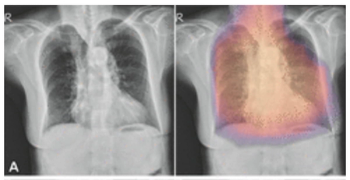

With reported increases in tuberculosis cases after the COVID-19 pandemic, the qSpot-TB adjunctive artificial intelligence (AI) device may facilitate improved diagnosis of the disease on chest X-rays.